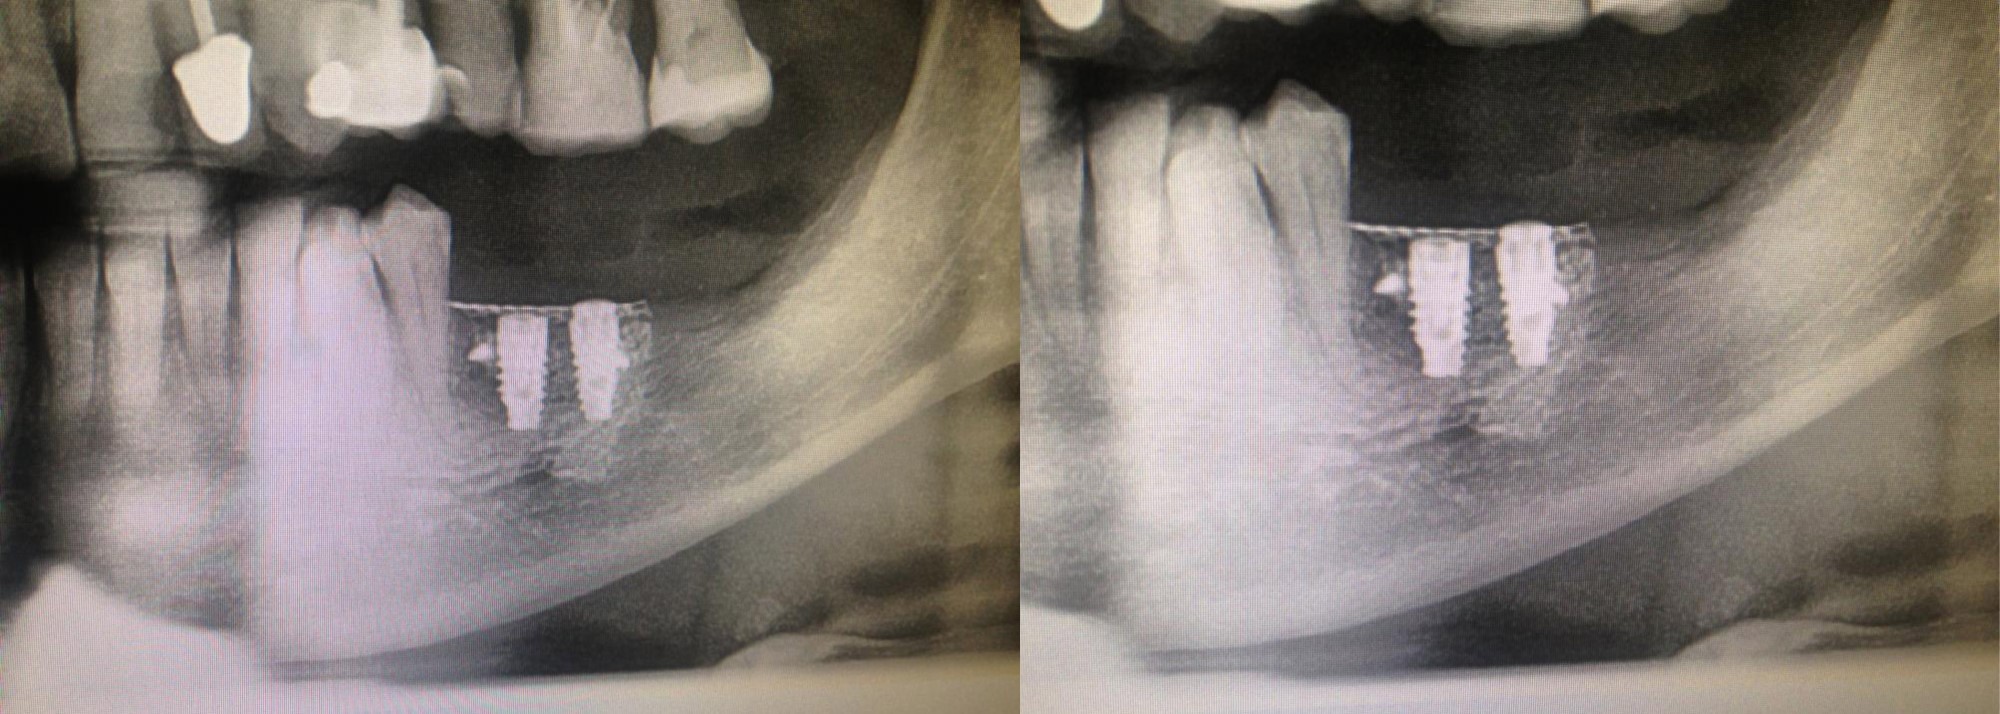

Inserimento di 2 impianti con rigenerazione ossea con griglie in titanio.

Impianti, dopo 6 mesi dall’intervento di ricostruzione ossea, pronti per essere protesizzati